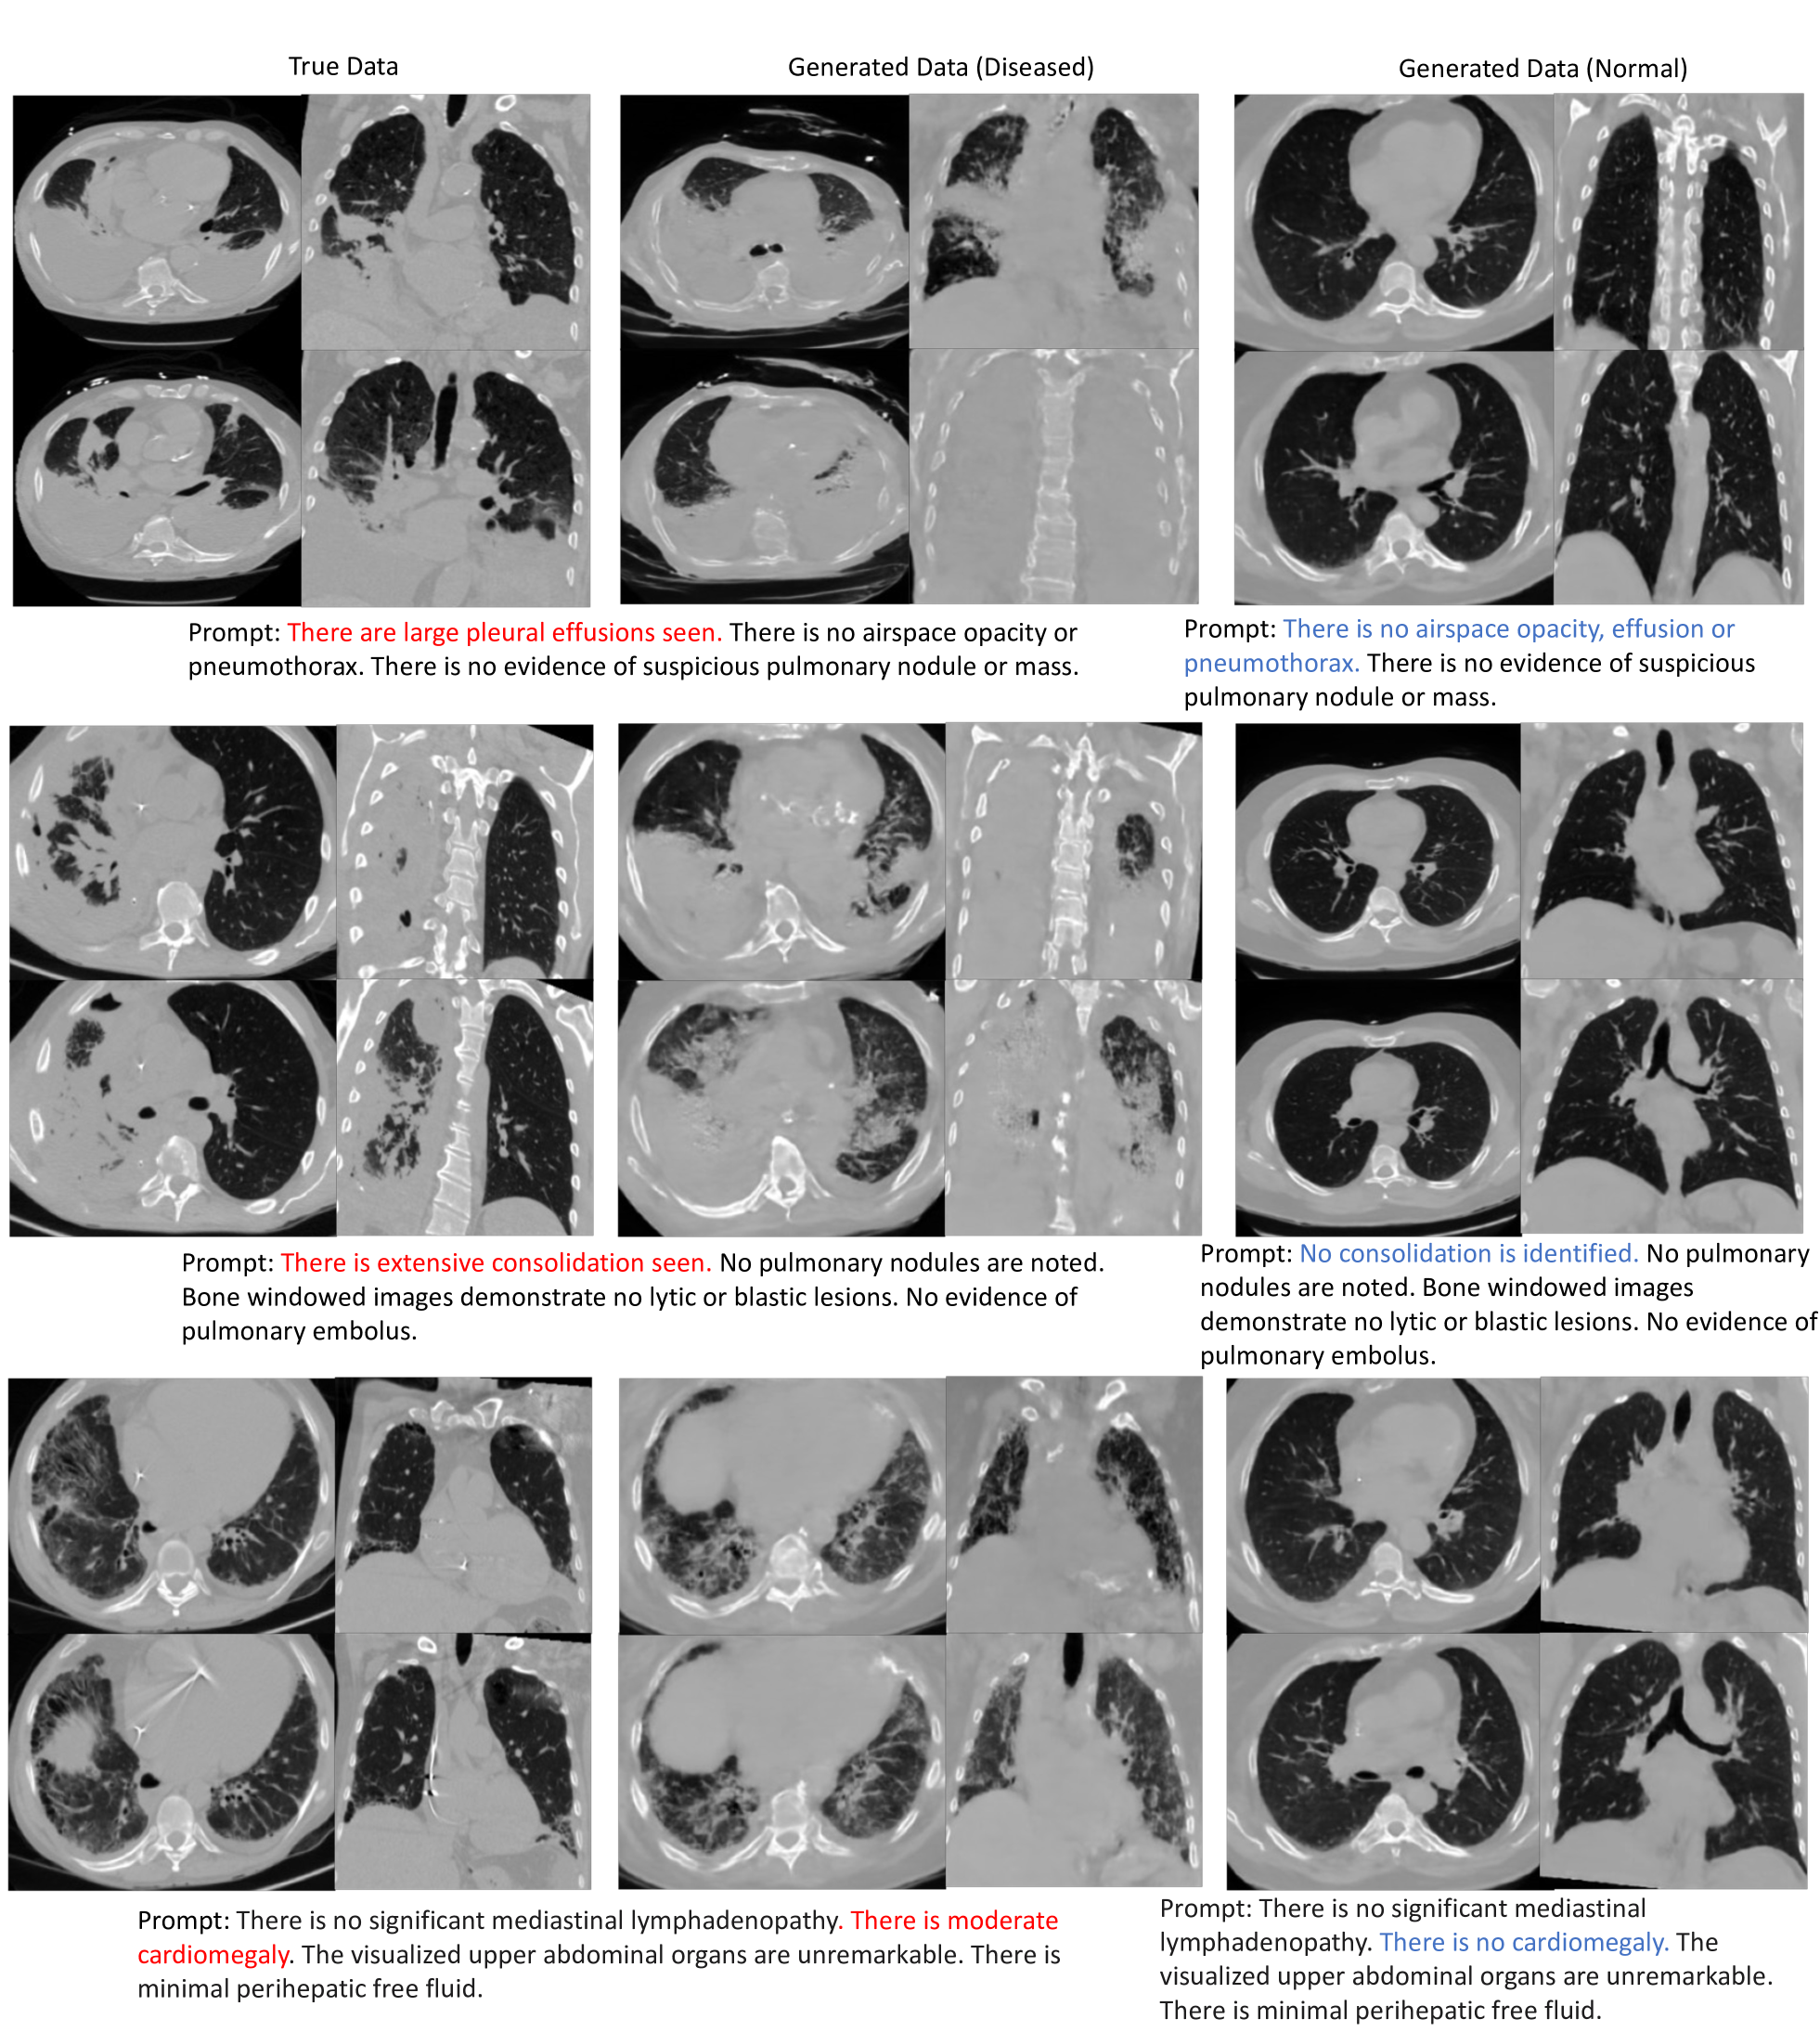

Refer to caption

Figure 4: Images conditionally generated with disease-related prompts. We show the real images in the first two columns. Then we extract disease-related mentions from their associated reports as conditions to generate images, which are shown in the third and fourth columns. We also show the synthesized samples by conditioning on prompts reversed of the disease in the last two columns. Four slices are shown for each subject. The generated images are conditioned on text only.

For the qualitative examples generated from our model, we chose those three distinct prompts paired with negative prompts to show the prompting effect on synthetic images. In Fig. 4, we show the volumes from the real and synthetic data with the text description and the negative prompting synthetic data. Our model shows the ability to generate unseen data and control the generative process through prompting.